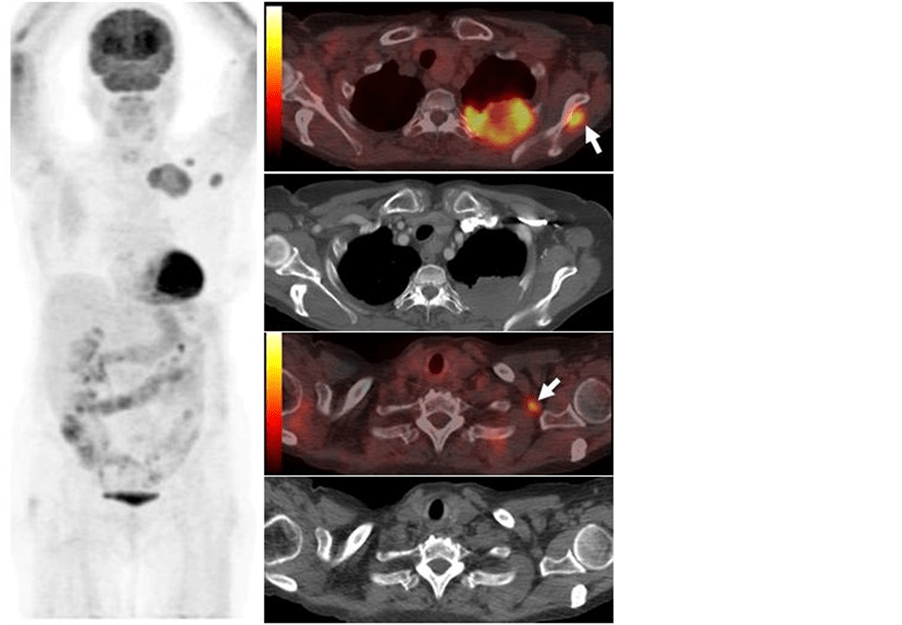

Pet Ct Scan For Lung Cancer . If lung cancer is detected at an early. A positron emission tomography (pet) scan uses a tracer with low levels of radiation to find places in your body where cells are unusually active—which can mean they're cancerous. Diagnosis is the process of finding out the cause of a health problem. This lets the doctor compare areas of higher radioactivity on the pet scan. Diagnosing lung cancer usually begins. At left is a ct scan, while the center image is a pet scan. Often a pet scan is combined with a ct scan using a special machine that can do both at the same time. Combining a pet scan with an mri or ct scan can help make the images easier to interpret.